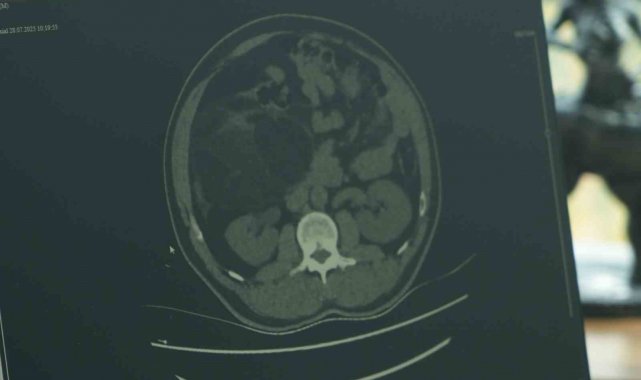

Samsun'da karın ağrısı şikayetiyle hastaneye başvuran erkek hastanın karnında tespit edilen 2 buçuk kilo ağırlığında ve 30 santimetre büyüklüğündeki kitle, yapılan başarılı operasyonla alındı. Nadir görülen bu vaka, erken teşhisin hayati önemini bir kez daha gözler önüne serdi.

Ameliyat, Samsun Büyük Anadolu Hastanesi'nde Genel Cerrahi Uzmanı Opr. Dr. Volkan Kınaş tarafından gerçekleştirildi. Hastaneye karın ağrısı şikâyetiyle başvuran 43 yaşındaki Özkan Ünal'ın yapılan tetkikler sonucunda, karın içinde yaklaşık 30 santimetre büyüklüğünde bir kitle tespit edildi. Pankreas, karaciğer ve böbrekle ilişkili bölgede yer alan dev kitle, yapılan operasyonla çıkarıldı.

Ameliyatı yapan Genel Cerrahi Uzmanı Opr. Dr. Volkan Kınaş, "Özkan Bey, hastanemize karında ağrı şikayetiyle geldi. Üroloji bölümüne başvurdu. Burada yapılan değerlendirmelerde hastanın karın içerisinde yaklaşık 30 santimetrelik bir kitle olduğu gözlemlendi. Bu kitle pankreas, karaciğer, böbrekle tamamen ilişkiliydi. Tabii, zor ve itina gerektiren bir ameliyattı. Bu tür vakalar çok nadir görülen, çok sık karşılaşmadığımız vakalardır. Gözden kaçırılmaması gereken ve ameliyatının titizlikle yapılması gereken vakalardır. Tüm hastalarımızda olduğu gibi kanser cerrahisinde de erken teşhisin önemi ve rolünden her zaman bahsetmek gerekir. Hastamız kendisi bu durumun farkına vararak bize geldi. Bu tip rahatsızlıkları geciktirmemek adına kişilerin sık sık checkup, tahlil ve tetkiklerini doktorlara giderek yaptırmaları gerekiyor" dedi.

Hasta Özkan Ünal ise "Daha önceden top oynarken karnıma darbe geldi. İç kanama oluştu ve ameliyat geçirdim. İkinci vakada da ağrılarım oldu. 5-6 gün sonra ağrılarım artınca hastaneye gelmek zorunda kaldım. Sağ olsun hocam her şeyimle ilgilendi. 30 santimlik kitleyi beklemiyordum, ben de çok şaşırdım" diye konuştu.

Samsun'da karın ağrısı şikayetiyle hastaneye başvuran erkek hastanın karnında tespit edilen 2 buçuk kilo ağırlığında ve 30 santimetre büyüklüğündeki kitle, yapılan başarılı operasyonla alındı. Nadir görülen bu vaka, erken teşhisin hayati önemini bir kez daha gözler önüne serdi.